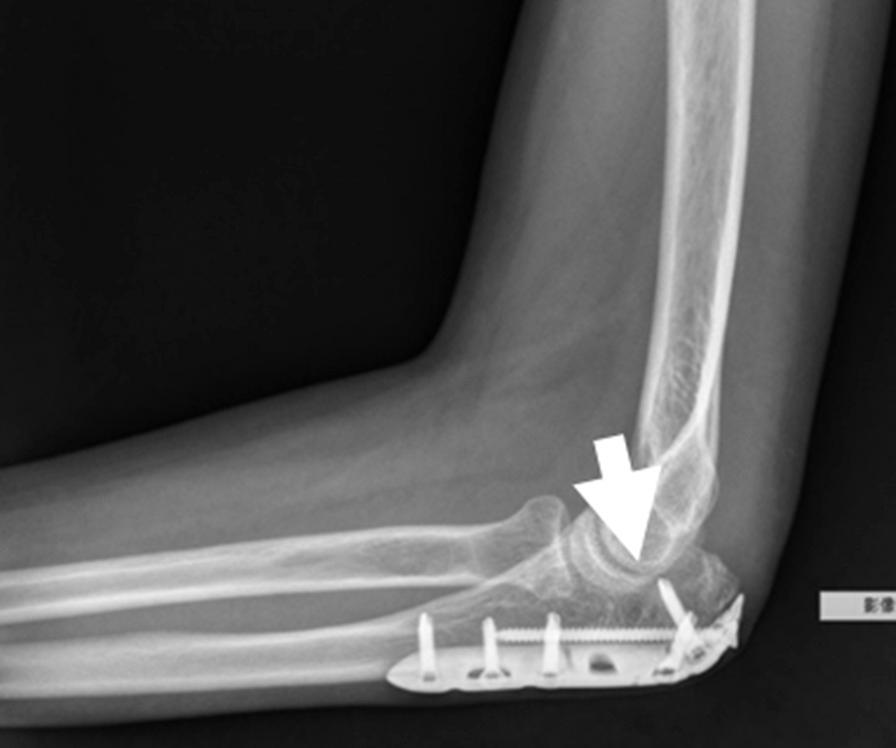

When a fracture goes into or around a joint, it usually damages the cartilage at the ends of bones and other joint tissue. As a result, the affected joints are prone to traumatic arthritis, leading to stiffness. Repairing bone damage, maintaining joint integrity, and avoiding subchondral and metaphyseal defects caused by comminuted fractures is often a great challenge for orthopedic surgeons. Tissue engineering of synthetic bone substitutes has proven beneficial to the attachment and proliferation of bone cells, promoting the formation of mature tissues with sufficient mechanical strength and has become a promising alternative to autograft methods. The purpose of this study is to retrospectively evaluate the clinical outcome and efficacy of a novel synthetic, highly biocompatible, and fully resorbable Ca/P/S-based bone substitute based on medical image findings.

A synthetic, inorganic and highly porous Ca/P/S-based bone-substituting material (Ezechbone® Granule, CBS-400) has been developed by National Cheng-Kung University. We collected fourteen cases of complex intra- and peri-articular fractures with Ezechbone® Granule bone grafting between 2019/11 and 2021/11. We studied the evidence of bone healing by reviewing, interpreting and analyzing the medical image recordings.

RESULTS

In the present study, CBS-400 was observed to quickly integrate into surrounding bone within three weeks after grafting during the initial callus formation of the early stage of repair. All of these cases healed entirely within three months. In addition, the patient may return to daily life function after 3.5 months of follow-up and rehabilitation treatment.

Ezechbone® Granule CBS-400 was proved capable of promoting bone healing and early rehabilitation to prevent soft tissue adhesions and joint contractures. Moreover, it has a high potential for avoiding ectopic bone formation or abnormal synostosis.